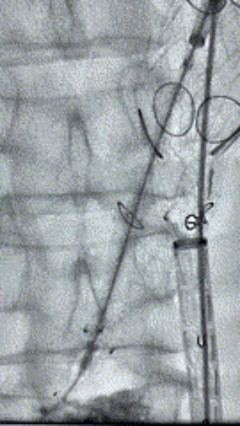

6. 解除束径,打开近端后释放,经肱动脉长鞘超选支架外分支,并进一步超选右侧肾动脉,交换加硬导丝,送入覆膜支架6*50mm和7*60mm各一枚,并予以球囊后扩张,手推造影显影良好。

7. 经长鞘重新选入左侧外分支,并超选进左肾动脉,沿导丝送入外周血管覆膜支架7*60mm一枚,并予以球囊后扩张,手推造影显影良好。

8. 从右侧股动脉入路送入腹主支架AB-24-12-110-S,近端重叠胸腹主动脉支架远端,调整好支架位置后释放。